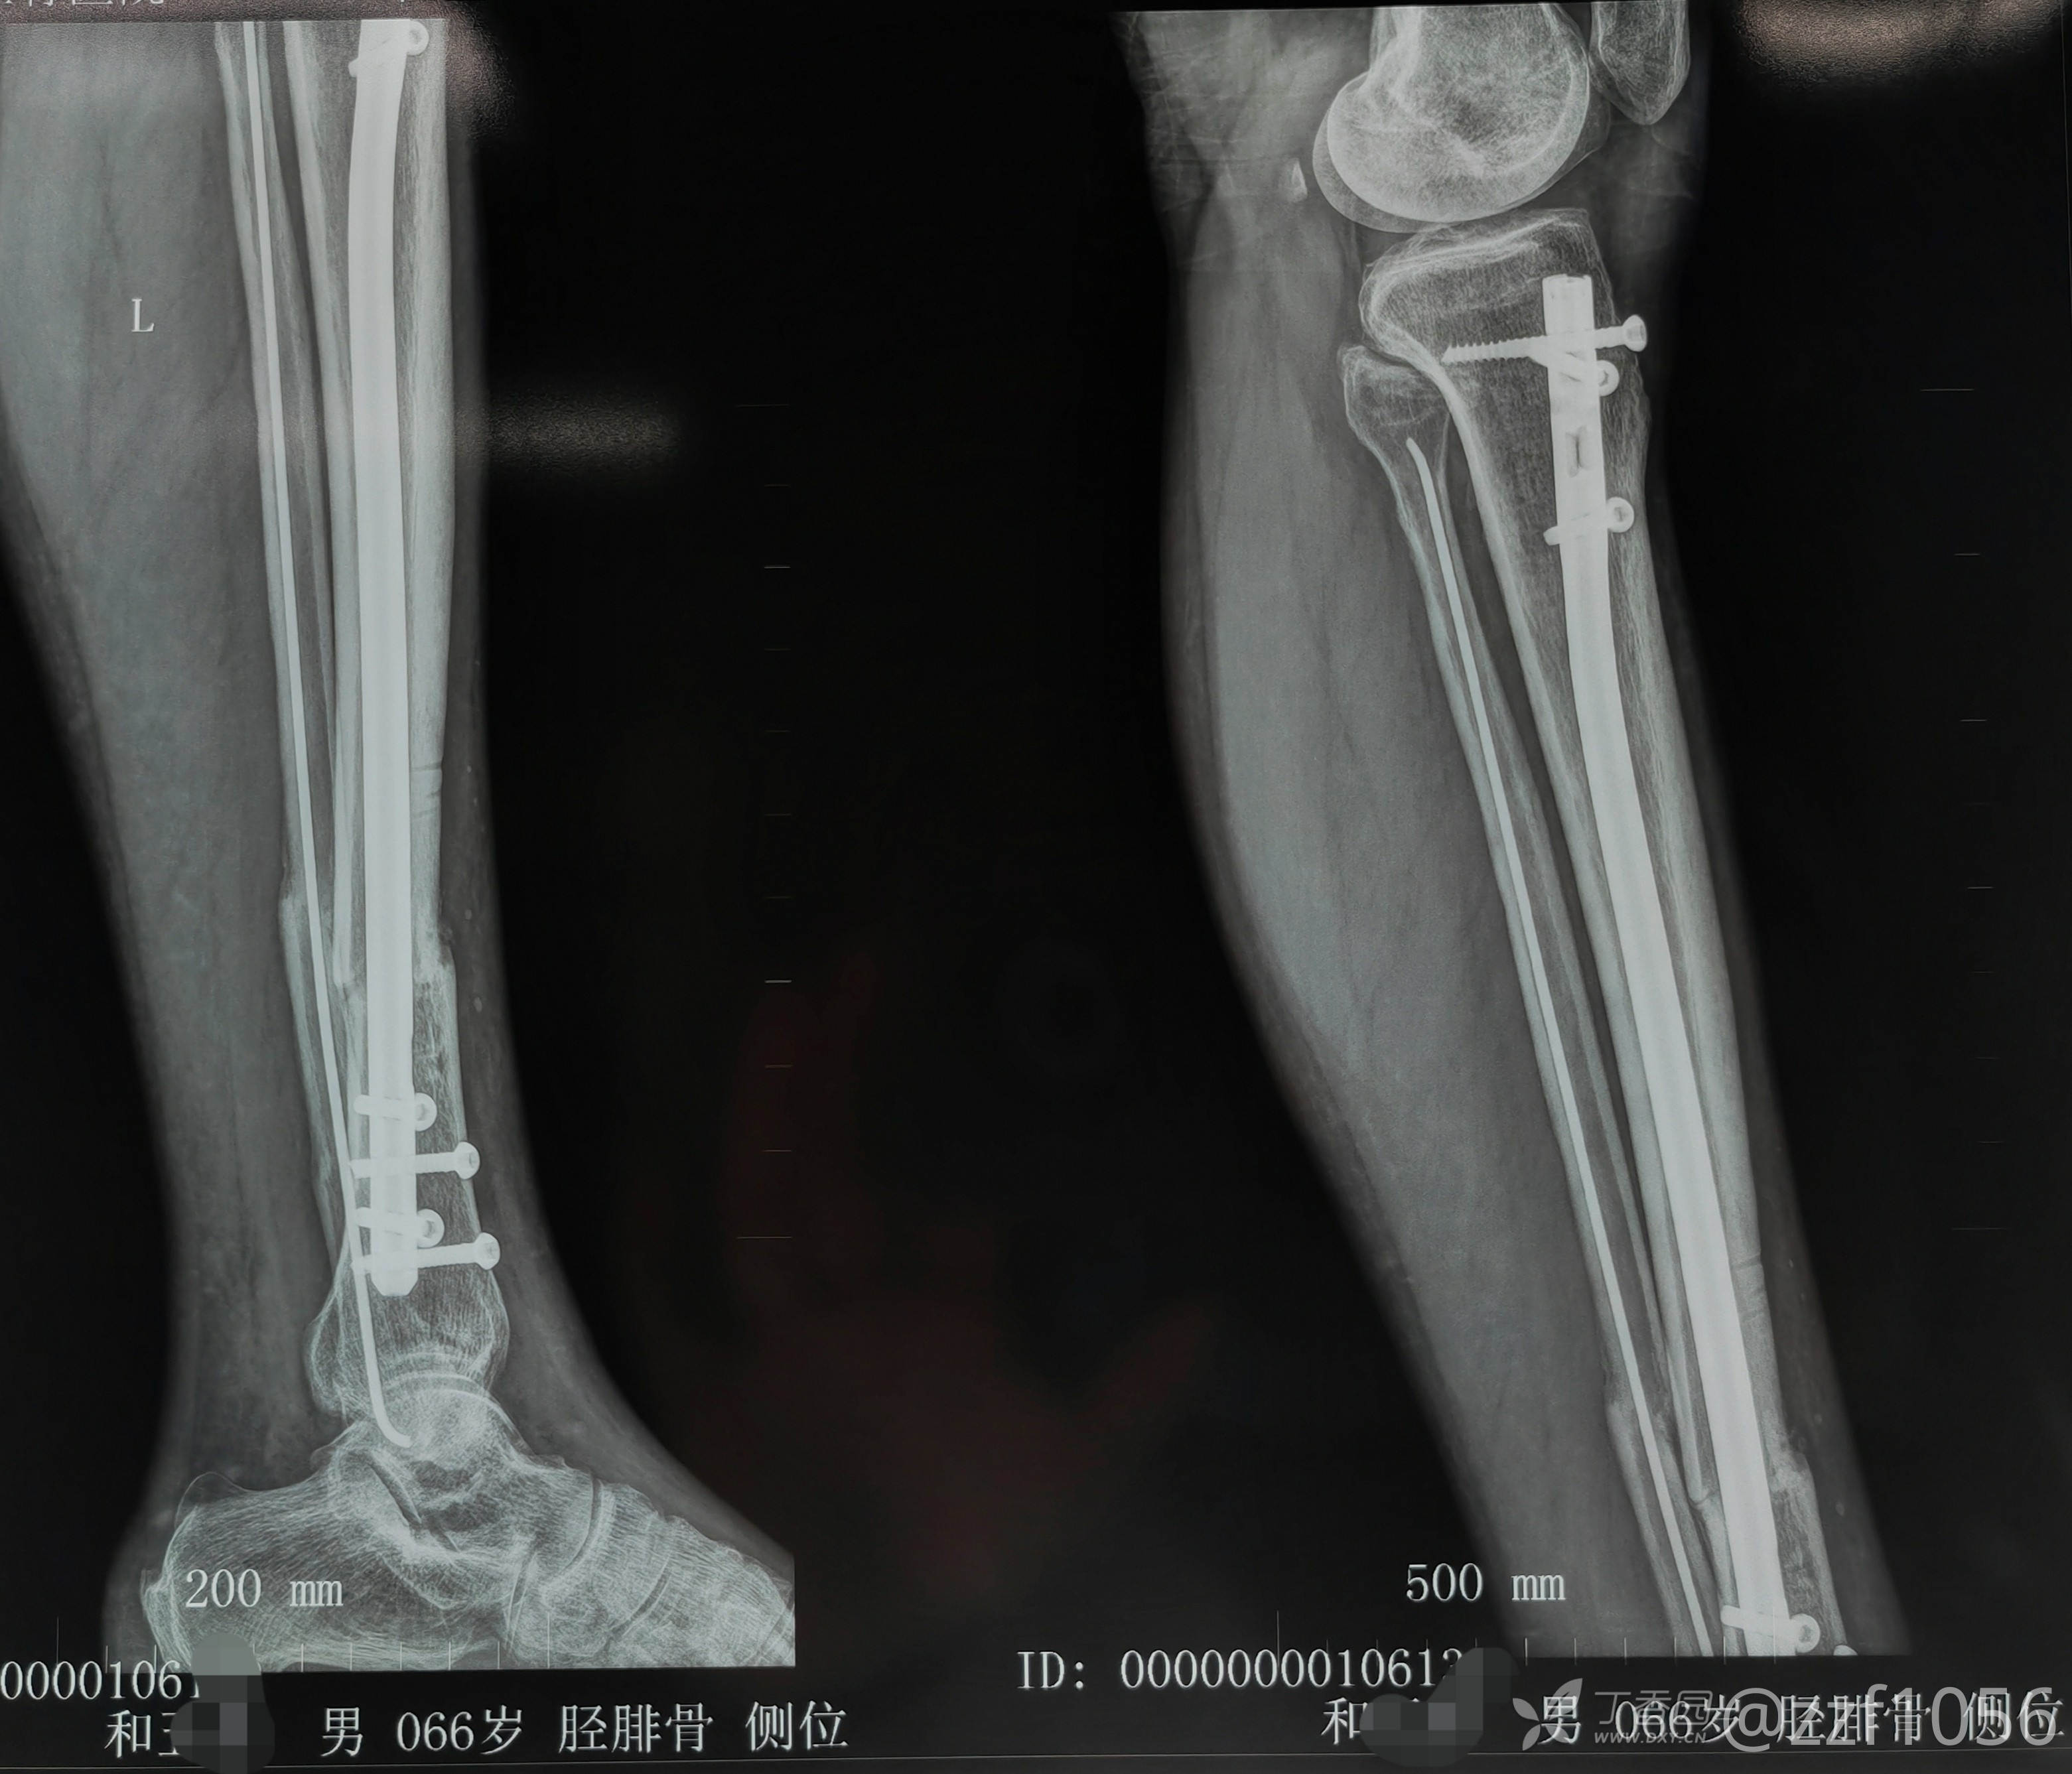

胫腓骨粉碎性骨折髓内钉及弹性髓内钉一例

术后八个月来院复查

这个胫骨向内成角对后期关节影响大吗?